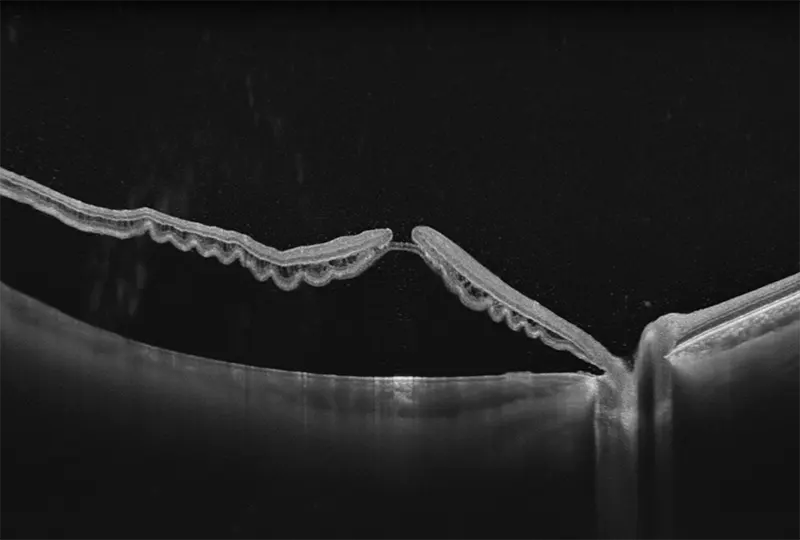

Galería OCTs del TowardPi Yalkaid